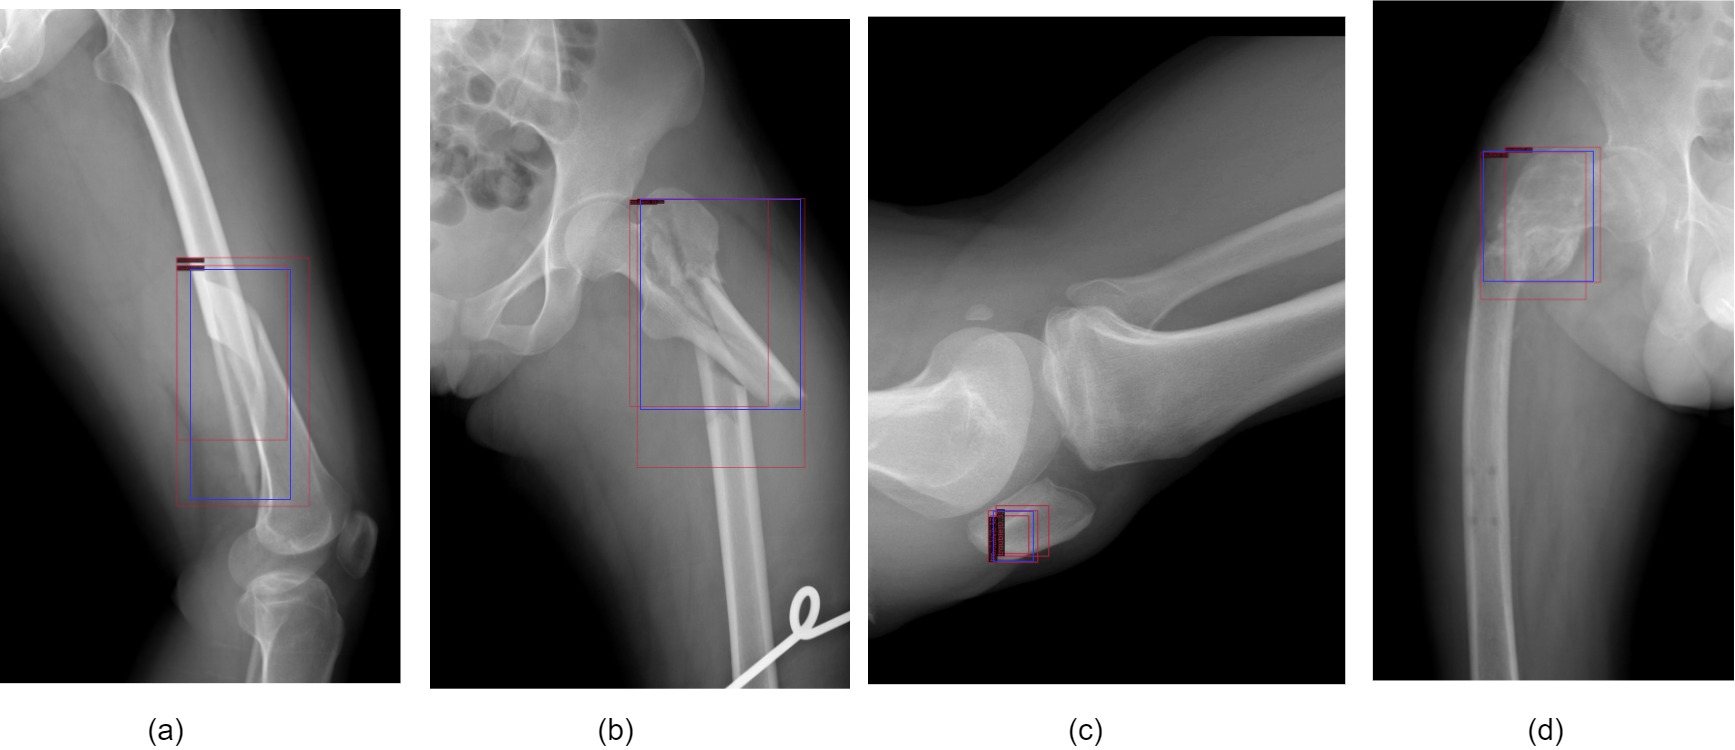

Refer to caption

Figure 6: blue: annotation; red: pseudo label.

Different from the classification quality evaluation of pseudo labels, the regression quality of pseudo boxes is a difficult index to evaluate. We visualized the pseudo labeled images of the teacher model in the training process, As shown in Figure 6. Because the prediction accuracy of the teacher model is not high enough, multiple pseudo boxes will be predicted around ground truth boxes of the unlabeled images. Most of these pseudo boxes can not provide reliable and accurate positioning information for student but after merging these pseudo boxes, the new box location is closer to the ground truth box. Therefore, we introduce Fusion Box module to reduce the inaccurate location impact of pseudo boxes. Specifically, for an unlabeled image predicted by teacher model, after confidence filtering, Fusion Box module select whether to synthesize each other through the similarity ξ𝜉\xi and the pseudo algorithm of Fusion Box is as Algorithm 1.